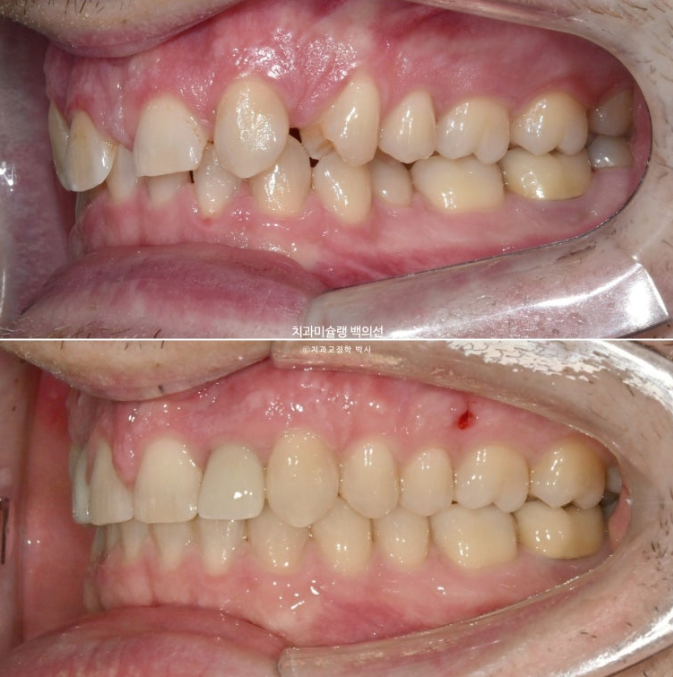

위 앞니 4개중 2개가 없습니다. 앞니가 크게 벌어져 있고 아래 앞니가 위로 솟아 위 입천장 잇몸을 칠 정도의 심한 과개교합이 있습니다.

만약 이렇게 선천적 결손치아와 돌출입이 혼재한다면 결손치아를 발치한 셈 치고 벌어진 공간을 모으며 돌출을 해소하는 방향으로 치료를 하기도 합니다.

하지만 환자분은 전형적인 caucasian의 안모를 보입니다.

즉 입술이 얇고 콧대가 높고 턱끝이 튀어나와 앞니가 뒤로 더 들어가면 큰일날 상입니다.

이런 경우라면 공간을 한쪽으로 몰아 결손치 자리에 임플란트를 하는 것이 좋습니다.

앞니 자리로 밀려온 송곳니를 원위치로 보내어 결손된 앞니자리에 임플란트 2개를 하기로 했습니다.

중심선은 잘 맞으며 쓰러진 앞니 뿌리 및 중절치 단차는 개선되었습니다.

어금니 교합도 양측 모두 1급 달성되었고 뜨는 부분도 없습니다.

중심선은 잘 맞고 과개교합은 깔끔하게 개선이 되었습니다.

어금니 교합은 물샐틈 없이 좋고 1급 교합관계를 보입니다.